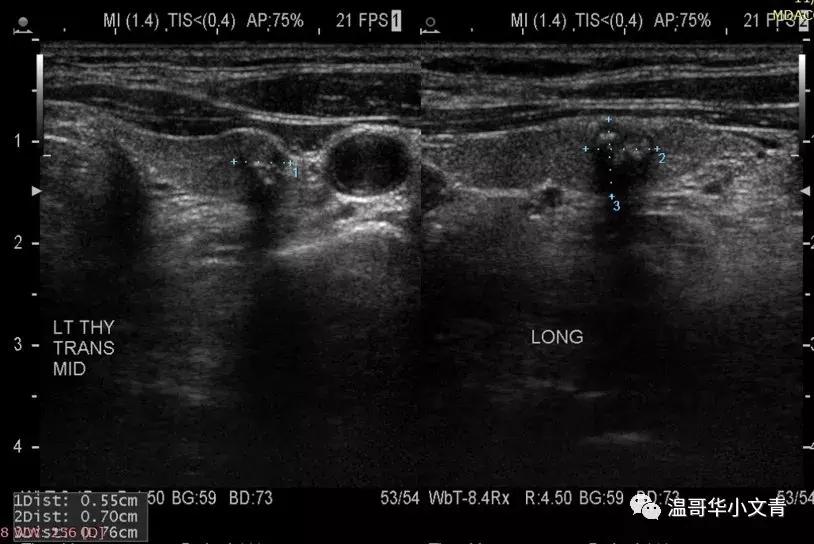

比如上图

肿瘤三个方位的直径分别是:0.55厘米,0.70厘米,0.76厘米

那肿瘤大小就符合观察的要求